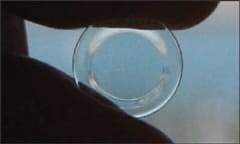

A 5X to 7X loupe may also be useful to inspect the surfaces. The surfaces will have a clean, highly reflective appearance if the patient is adequately cleaning them (Figure 2).

Figure 2. An adequately cleaned corneal reshaping lens.